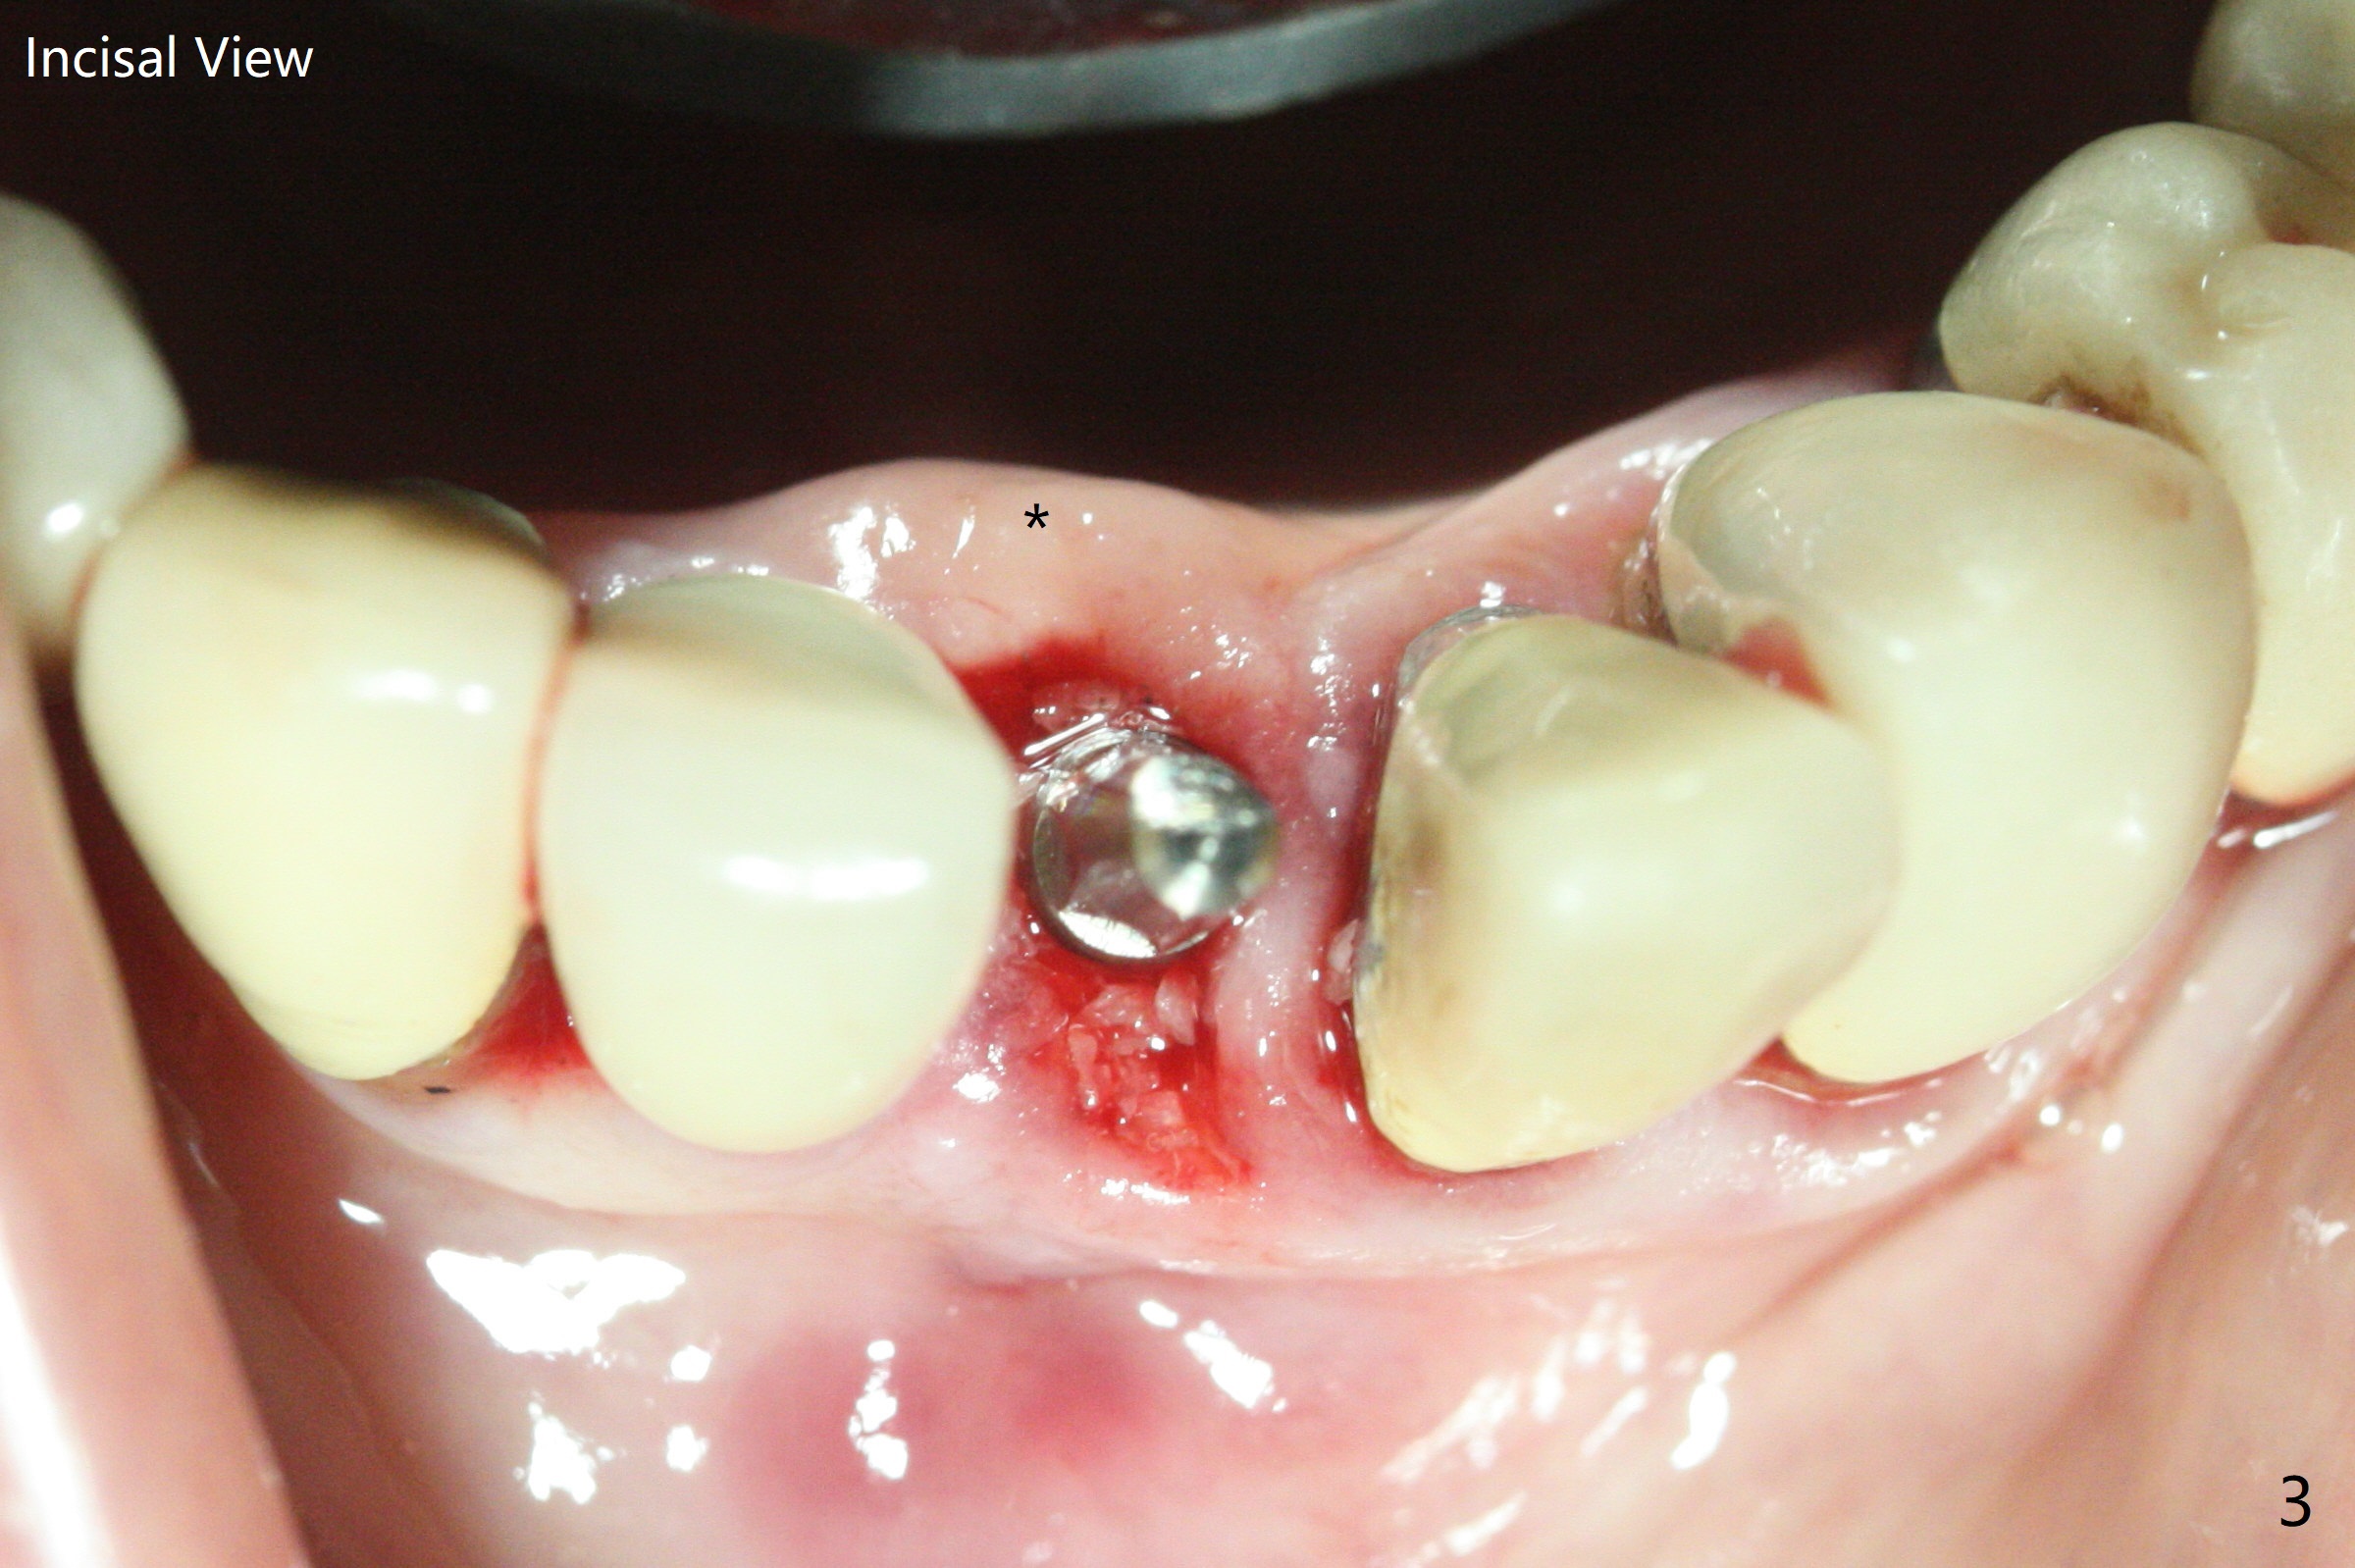

After extraction of the tooth #24 with vertical root fracture (loss of buccolingual plates), osteotomy is initiated with 1.2 mm drill free hand; the trajectory seems satisfactory (Fig.1). With sequential osteotomy, a 2.5x14(2) mm 1-piece implant has difficulty being placed deep (Fig.2), apparently associated with dense bone. Allograft is placed not only mesiodistal (Fig.2,4 *), but also buccolingual (Fig.3,5,6 *) to cover the exposed implant threads. In fact inability to place the implant deep is due to the apex of the implant (Fig.5,6 x) touching the lingual (L) cortical plate. If surgical guide were used, the implant placement difficulty would not occur. The surgery would be shorter and easier. The seemingly easiest implant placement should be assisted with a guide! In addition, preop CT would dictate implant placement in the middle of the socket buccolingual. The lingual (Fig.7 *) and buccal (Fig.8 <) gingiva remains bulky, although asymptomatic, 8 days postop.